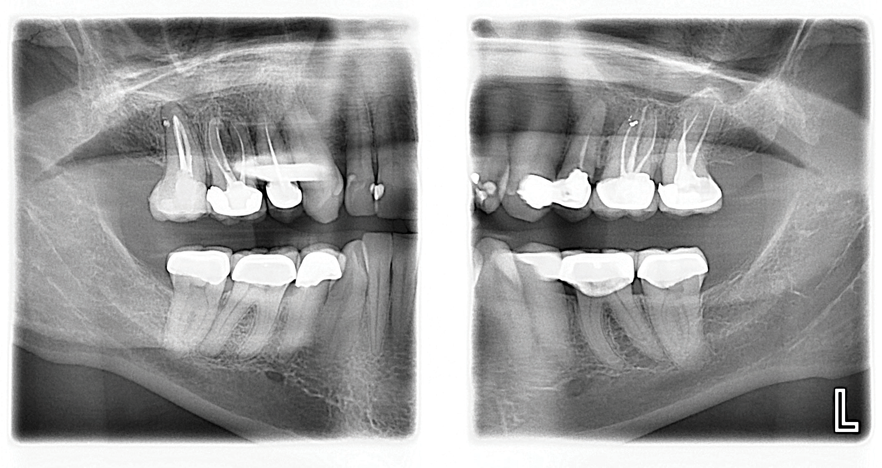

In another case, a 57-year-old patient presented with sensitivity for 6 months on tooth No. 18 which was increasing (Figure 3 and Figure 4). The clinician adjusted it to determine there was no occlusal component compounding the sensitivity. However the patient continued to experience sensitivity. To provide the patient relief, two applications of SDF were recommended. After the first application, which required only 10 minutes, the patient experienced a considerable decrease in sensitivity. A follow-up application of SDF two weeks later resulted in an additional charge for the placement of SDF, which added to the production of the appointment. The patient left with resolution of her complaint.

(3.) Patient presented with sensitivity for 6 months on tooth No. 18.

Figure 3

(4.) Patient presented with sensitivity for 6 months on tooth No. 18.

Figure 4